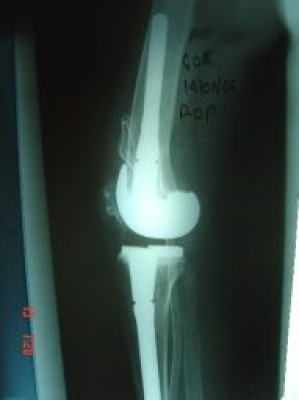

Revisión de prótesis de rodilla

Envíado por Dr. Ricardo Antonio Gómez G.